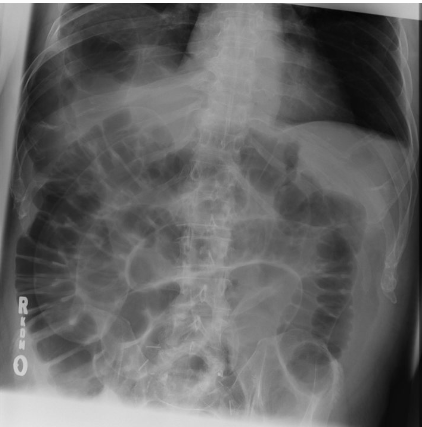

Thumbprinting sign is suggestive of _____

The thumbprinting sign is seen in both _____ colitis and _____ colitis.